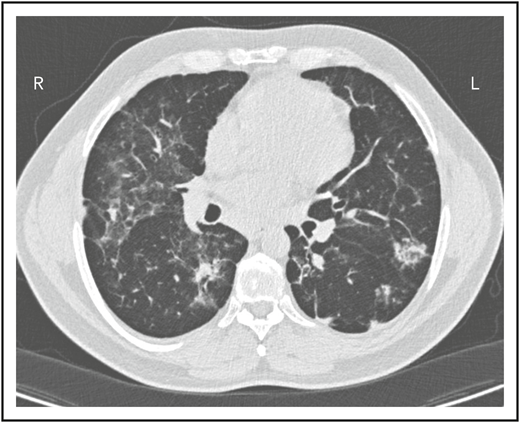

A second common reason for a patient to come to the attention of hematologists is the finding of an enlarged spleen, especially in an adult with lymphadenopathy. This was the reason in patient 2, who is now a 46-year-old male professional dog walker. At the age of 31, he was found to have an enlarged spleen together with cervical and axillary lymphadenopathy. Hematology was consulted, and the lymph node was biopsied; pathology revealed that he had noncaseating granuloma. He was then referred to pulmonology and, with this evidence, was diagnosed with sarcoidosis and treated with steroids for some months, but he stopped the treatment. Although he had no obvious respiratory symptoms over the following 15 years, he had a slow decline in lung function, and chest computed tomography showed hilar lymphadenopathy, ground-glass opacities with nodules, and bronchiectatic changes (Figure 2). In 2018, he had acute bacterial pneumonia, became concerned, and found on the internet that granulomata in the lungs and an enlarged spleen might be related to low serum immunoglobulin levels. He asked that this be tested; when this test was performed, he had striking low serum immunoglobulins: IgG, 97 mg/dL; IgA, <5 mg/dL; IgM, 27 mg/dL. However, within the month, he was hospitalized for pneumonia due to metapneumovirus. The diagnosis of CVID was finally made, and immunoglobulin treatment was started. The patient’s spleen remains large.

The patient in clinical case 2 had a slow decline in lung function due to his immune defect, but this was assumed to be due to sarcoidosis. Chest computed tomography showed ground-glass opacities with numerous nodules, hilar lymphadenopathy, and bronchiectatic changes. With granuloma on biopsy, these changes were consistent with granulomatous lymphocytic interstitial lung disease.